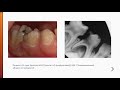

Острый пульпит. Этиология, патогенез. Классификация. Клиника. Диагностика. Лечение.

Эндодонтия 3. Воспаление пульпы. Этиология, патогенез, классификация